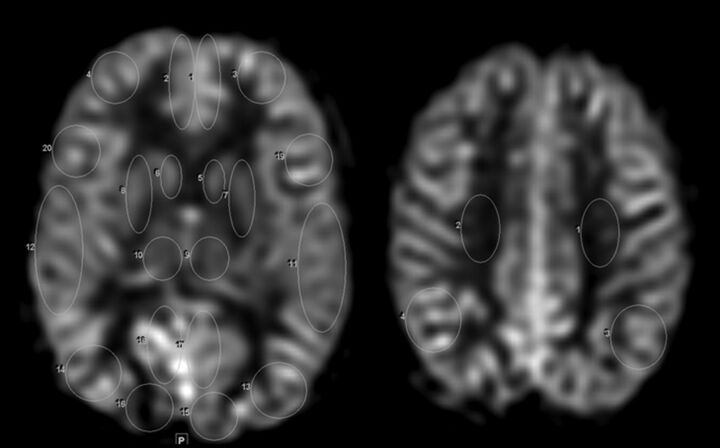

Quantitative cerebral cortical CBF was measured at 2 axial sections at the level of the thalamus and the centrum semiovale. Fourteen cortical ROIs and 4 ROIs of the deep gray nuclei were obtained at the level of the thalamus; an additional 4 ROIs were obtained at the level of the centrum semiovale, as shown in Fig 1. These regions included anterior and posterior cingulate gyri, medial frontal lobe, frontal operculum, anterior caudate nucleus, globus pallidus, thalamus, superiomedial temporal cortex, temporo-occipital cortex, occipital cortex, centrum semiovale, and parietal cortex. The ROI sizes ranged from 100–800 mm2, depending on the size of the structure interrogated. A board-certified neuroradiologist (K.W.Y.) with added Certificate of Added Qualification (7 years of experience) selected ROIs, blinded to clinical information and at the same anatomic levels in all patients. A second blinded board-certified neuroradiologist (P.D.B.) with a Certificate of Added Qualification (>30 years of experience) independently confirmed appropriate anatomic placement of the ROI. To test for significant differences in CBF between the patients and control subjects, comparison by Mann-Whitney test was used, with Bonferroni-adjusted P value ≤.004 judged as significant. To test for difference in cerebral perfusion in the brain regions between the sedated and nonsedated groups, as well as between boys and girls, independent samples of the Mann-Whitney test were used, with Bonferroni-corrected α = 0.004 (for 12 comparisons).

Fig 1.

Brain ROI placement. ROI placement is shown in the cortical regions of the bilateral cerebral hemispheres, the deep gray nuclei, and in the centrum semiovale at 2 axial levels: at the level of the thalamus and centrum semiovale.